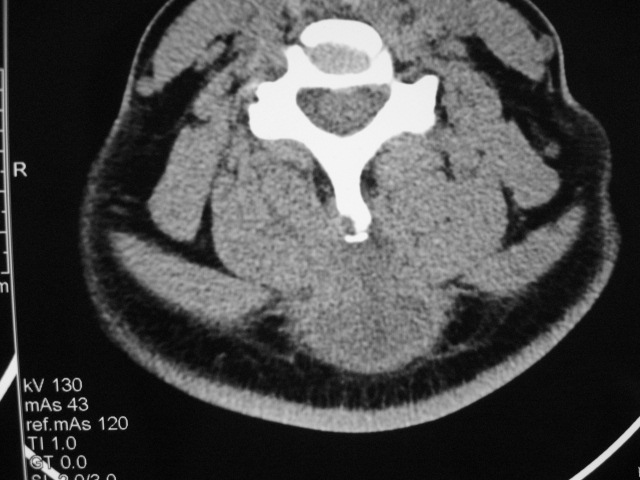

女,46岁,发现颈后区肿块3月余.

颈后软组织肿块,内可见坏死区及点状钙化,邻近颈椎棘突可见破坏,邻近肌间隙模糊,肿块周围脂肪间隙可见索条状影。

考虑:1)感染,结核可能;

2)肿瘤不能排除。

颈后部结核性脓肿可能性大,侵犯临近颈椎棘突,建议进一步检查并照胸片。